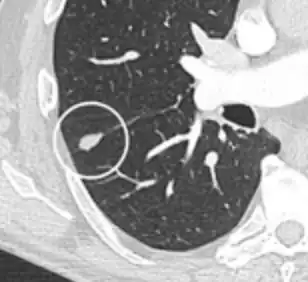

- Margin morphology: a spiculated margin is a risk factor for cancer.[8] Benign causes tend to have a well defined border, whereas lobulated lesions or those with an irregular margin extending into the neighbouring tissue tend to be malignant.[10] In particular, spiculations are highly predictive of malignancy with a positive predictive value up to 90%.[9] Also, a "notch sign", which is an abrupt indentation of the nodule, increases the risk of cancer, but may also be found in granulomatous diseases.[9]

subpleural nodule.[9] -

Round well-delineated solid lung nodule with smooth border.[9] -

Lobulated nodule.[9] -

Spiculated lung nodule.[9] -

A "notch sign".[9] -

A triangular perifissural node can be diagnosed as a benign lymph node.[9]